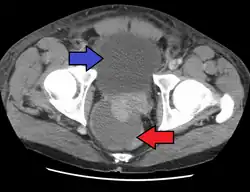

Abscess of the prostate (red arrow) resulting in urinary retention (blue arrow)

Acute prostatitis is relatively easy to diagnose due to its symptoms that suggest infection. The organism may be found in blood or urine, and sometimes in both.[2] Common bacteria are Escherichia coli, Klebsiella, Proteus, Pseudomonas, Enterobacter, Enterococcus, Serratia, and Staphylococcus aureus. This can be a medical emergency in some patients and hospitalization with intravenous antibiotics may be required. A complete blood count reveals increased white blood cells. Sepsis from prostatitis is very rare, but may occur in immunocompromised patients; high fever and malaise generally prompt blood cultures, which are often positive in sepsis. A prostate massage should never be done in a patient with suspected acute prostatitis, since it may induce sepsis. Since bacteria causing the prostatitis is easily recoverable from the urine, prostate massage is not required to make the diagnosis. Rectal palpation usually reveals an enlarged, exquisitely tender, swollen prostate gland, which is firm, warm, and, occasionally, irregular to the touch. C-reactive protein is elevated in most cases.[4]

Severely ill patients may need hospitalization, while nontoxic patients can be treated at home with bed rest, analgesics, stool softeners, and hydration. Men with acute prostatitis complicated by urinary retention are best managed with a suprapubic catheter or intermittent catheterization. Lack of clinical response to antibiotics should raise the suspicion of an abscess and prompt an imaging study such as a transrectal ultrasound (TRUS).[7]